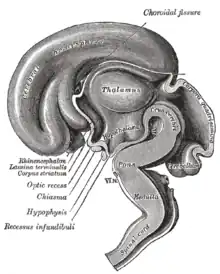

Comme son nom l'indique, cet organe est situé en dessous du thalamus, juste au-dessus du tronc cérébral et forme la partie ventrale du diencéphale. Tous les vertébrés possèdent un hypothalamus. Chez l'humain, il est à peu près de la taille d'une amande.

Anatomie

L'hypothalamus fait partie de la portion inférieure du diencéphale. Il forme les parois inféro-latérales et le plancher du 3e ventricule, situé sous le thalamus (d'où son nom), dont il est séparé par le sillon hypothalamique (de Monro). Il est en rapport, par ailleurs, avec la région sous-thalamique, en dehors via le champ tegmental de Forel, en avant par la lame terminale, et en arrière par le tegmentum mésencéphalique.